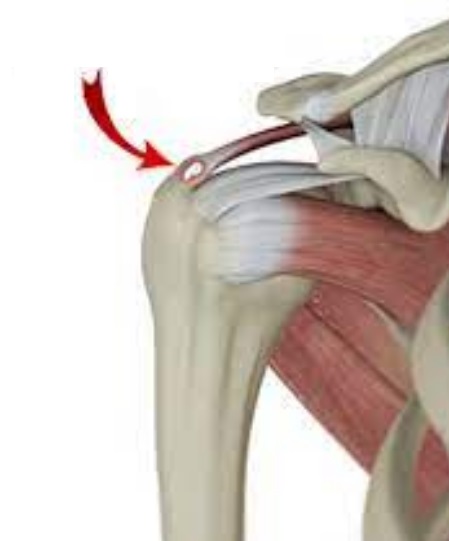

석회성 힘줄염은 말 그대로 어깨 힘줄에 석회(칼슘)가 침착되어 염증을 일으키는 질환이에요. 아직까지 정확한 원인은 밝혀지지 않았지만, 주로 힘줄의 퇴행성 변화나 미세한 손상, 혈류 감소 등이 원인으로 지목되고 있습니다. 30~50대 연령층에서 비교적 흔하게 나타나는데, 특히 어깨를 많이 사용하는 직업이나 반복적인 운동을 하는 분들에게 더 잘 생긴다고 해요. 꼭 나이가 많아야 생기는 건 아니라는 거죠.

석회성 힘줄염은 통증이 자연스럽게 사라지는 경우도 있지만, 방치하면 만성 통증으로 이어지거나 어깨 힘줄 파열로 진행될 수 있으니 꼭 전문가의 진료를 받아보는 게 중요해요.